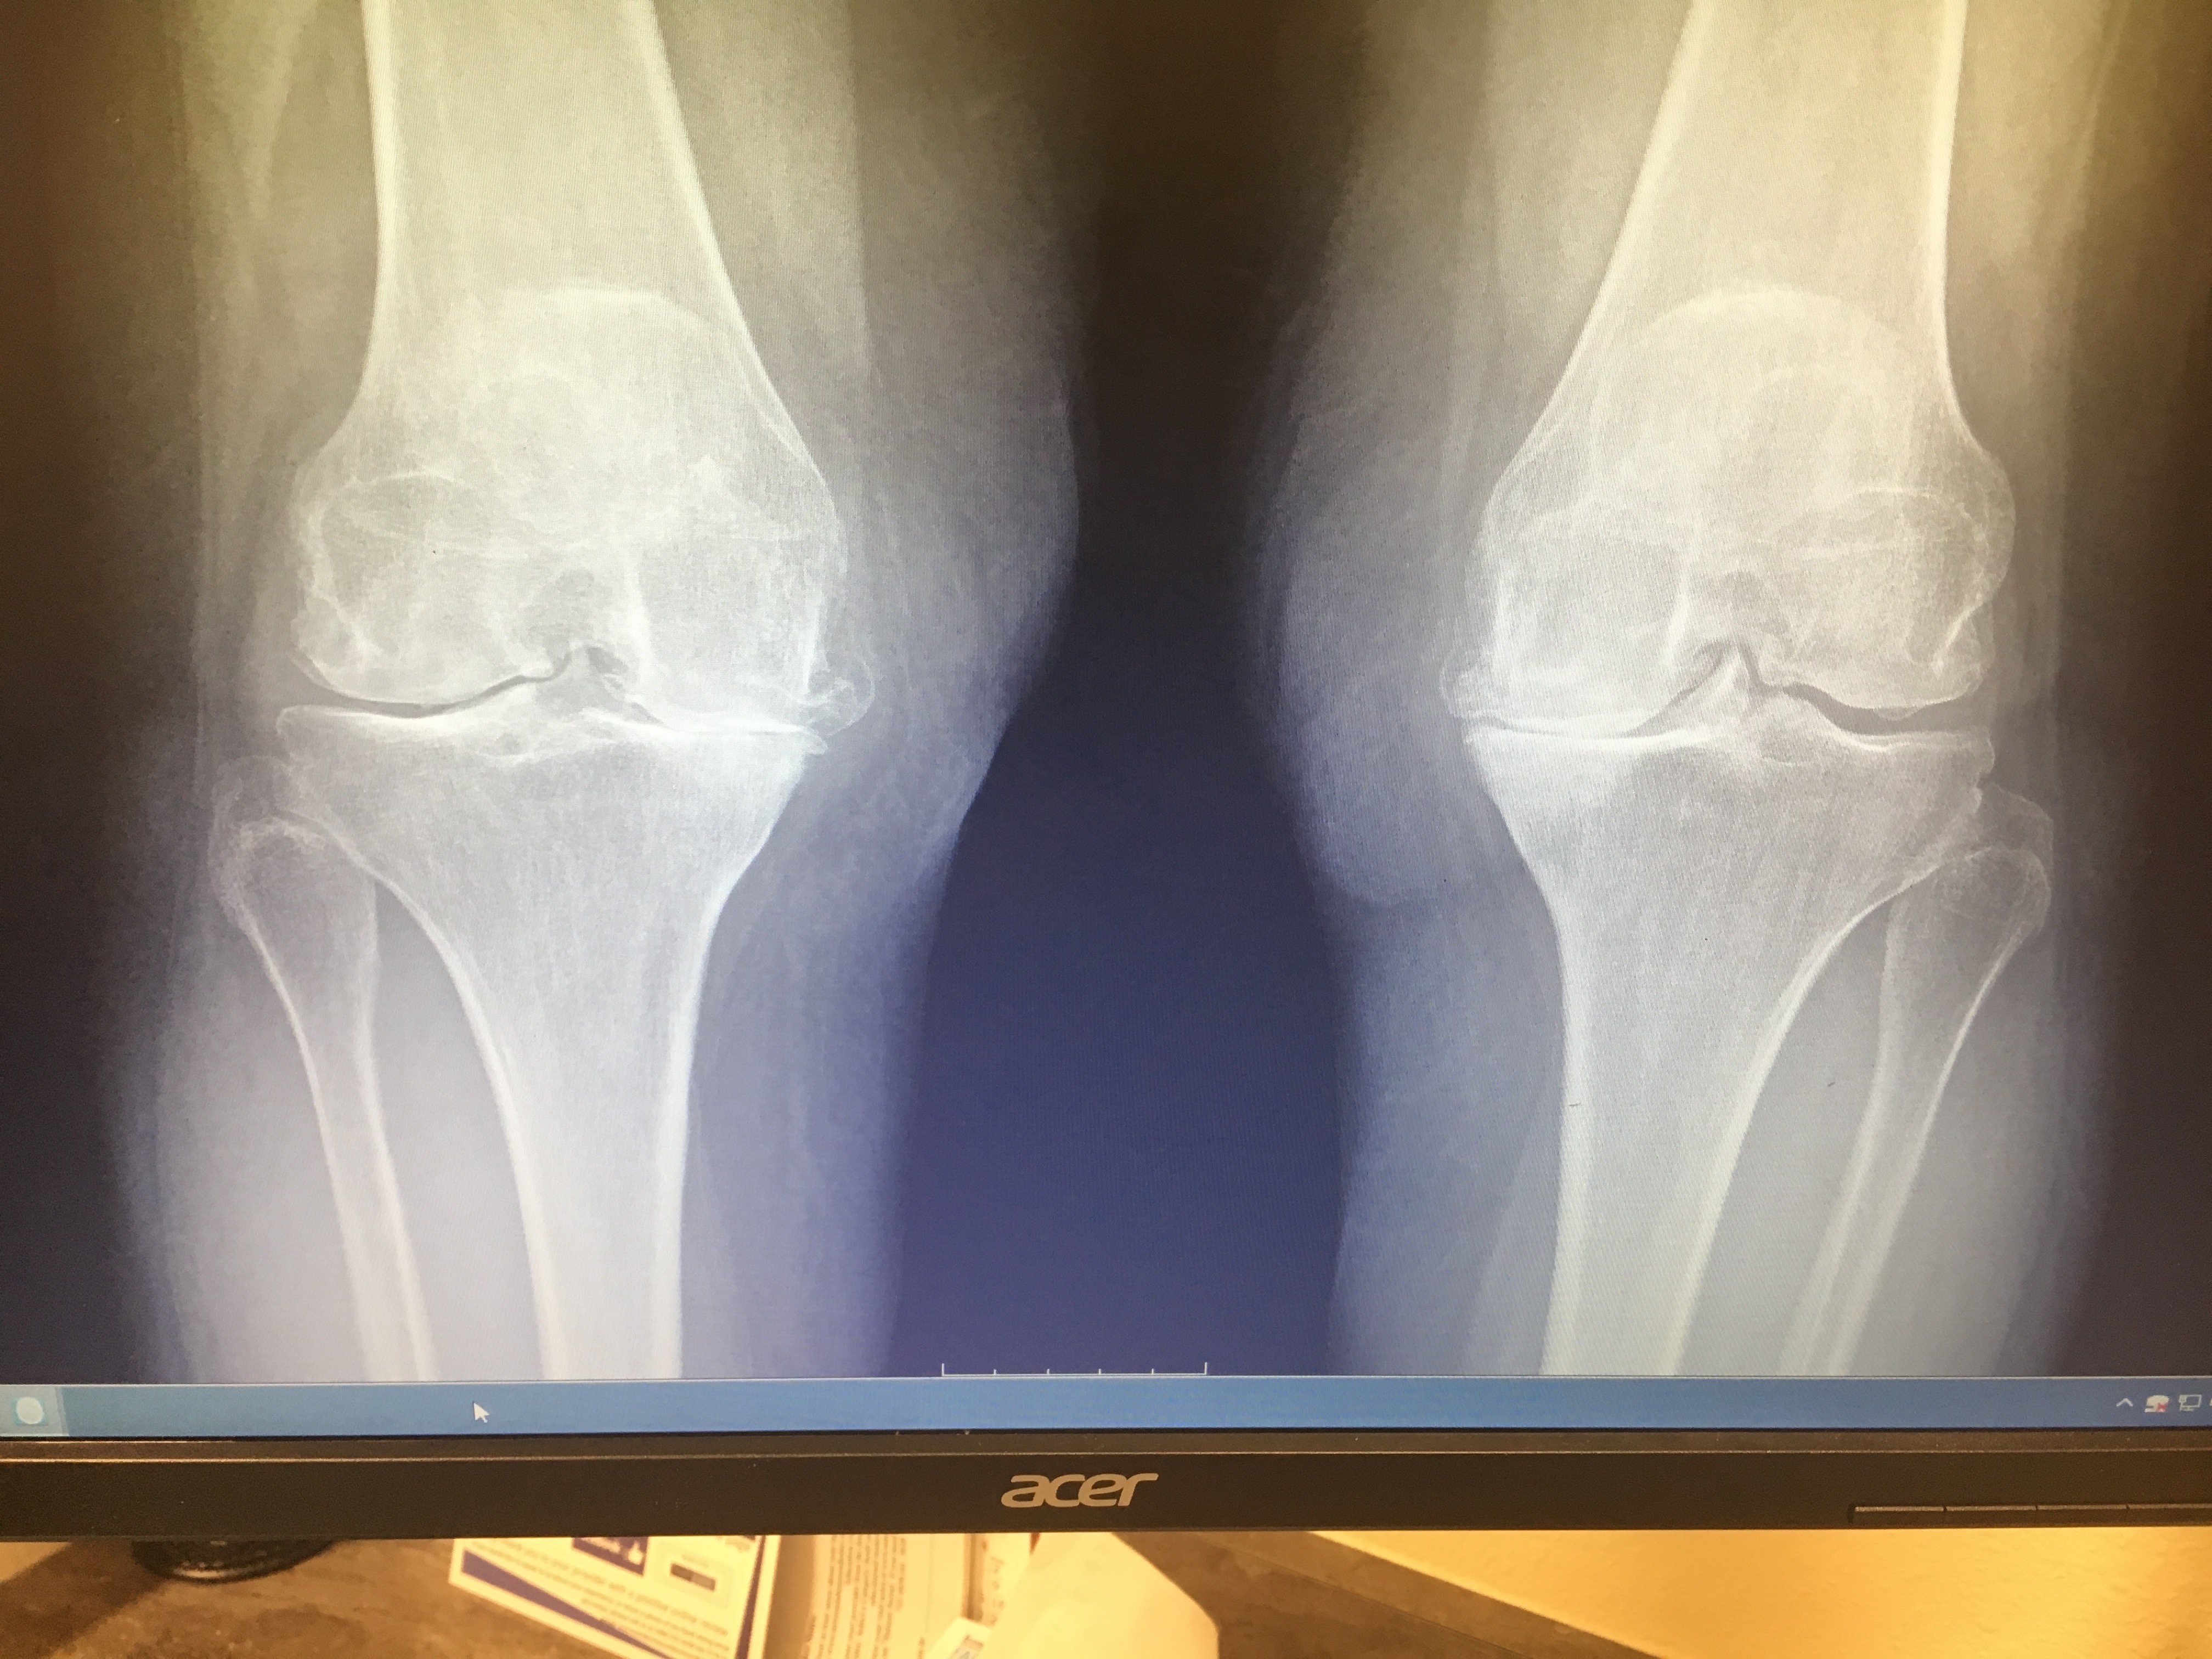

I am 67 years old and I can barely walk. My knees have no cartilage and lots of arthritis and bone spurs!! It’s unbelievably painful!! My orthopedic surgeon said that my knees are some of the worst he’s ever seen!!